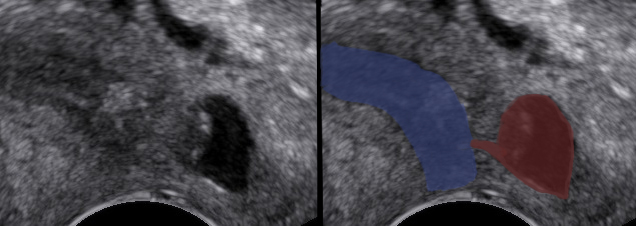

An 80-year-old female patient presents with persisting overactive bladder symptoms. After careful ultrasound examination, a unilocular cystic mass with a single urethral connecting tract containing a calculus was identified as an urethral diverticulum.

Clinical Image

L (distal) / N (1)/ S (1cm) / C (single) / C (distal) / C (overactive bladder)